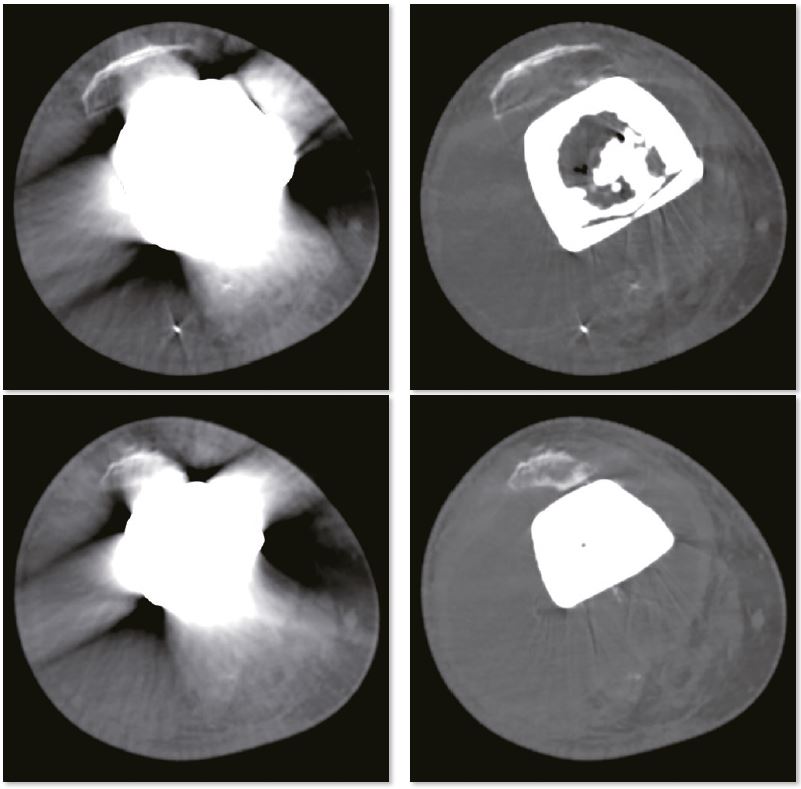

Заміна колінного суглоба

Для стабілізації заднього відділу хребта та збереження хребетного каналу використовується внутрішня фіксація. Зображення SEMAR забезпечують чудову деталізацію хребетного каналу без артефактів. Міжхребцеві дискові простори звужені та дегенеративні в цій частині поперекового відділу хребта

3D зображення коліна

Звичайне зображення

Зображення з SEMAR